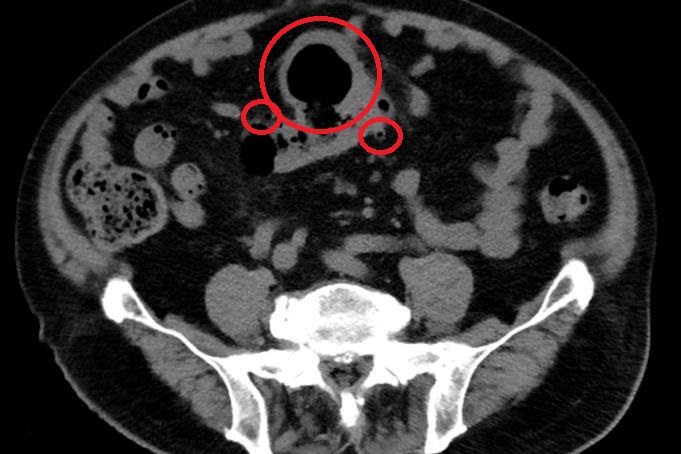

大腸直腸外科陳信宏醫師從電腦斷層發現大腸有多處憩室,合併乙狀結腸有一個巨大囊狀腫塊,甚至產生腹水,其中產生的憩室最大也已至7-8公分,經檢體取樣排除惡性腫瘤的可能後,以微創腹腔鏡手術切除乙狀結腸,五天後,趙先生平安出院,現已不再腹痛。

▲電腦斷層顯示大腸已有多處憩室。(示意圖/台北慈濟醫院)